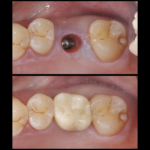

痛くない虫歯・・?

こんにちは!院長の渡辺です。 本格的な寒波がきていますが体調崩されたりしてないでしょうか? 風邪をひくと咳や熱がでますね、転んで擦りむくと痛みや血がでます。 虫歯はどうでしょう?冷たいものがしみたり、ずきずきしたりといった症状があればわかりやすいですが。。 実は無症状に進む虫歯もあります。 特に大人は歯の中にある神経が子供に比べると細いので痛みがですそのままじわじわと進行していくことも珍しくありま...